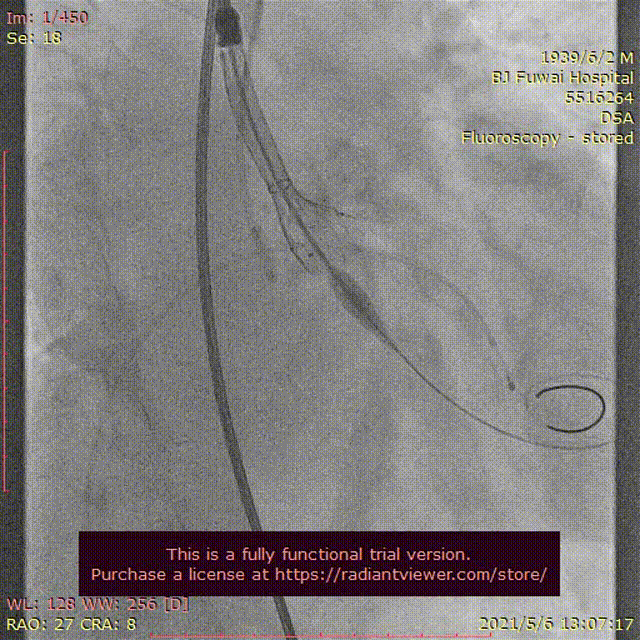

图3患者经导管主动脉瓣置换术及围术期操作

A:主动脉根部造影;B:23 mm球囊预扩张;C:26型号VenusA瓣膜植入;D:26型号VenusA“瓣中瓣”位置良好,少量瓣周漏;E和F:术前及术后经导管跨瓣压差;G:肘正中静脉留置针;H:患者全程清醒状态。

根据瓣上结构测量及球囊预扩张效果,采取“Down-size”策略,选择A-26 Venus A瓣膜,通过输送系统完成过弓和跨瓣;Venus A瓣膜精准定位于瓣环水平,

在临时起搏器控制心室快速起搏下完成瓣膜释放;

由于本例患者原瓣叶融合钙化较重,采用“瓣中瓣”技术植入另外一个A-26 Venus A瓣膜,

采用23mm NUMED-II球囊对植入的瓣膜进行后扩张;

最后造影显示新植入的瓣膜位置理想,少量瓣周反流,

跨瓣压差由术前30 mmHg下降至4 mmHg;即刻经胸超声评估主动脉瓣位植入生物瓣峰值流速为2.0 m/s,平均跨瓣压差为16 mmHg,少中量瓣周反流,左室射血分数为45%;评估患者心率为67次/分并且心电图较术前无明显异常,故即刻拔出临时起搏导线。整个手术过程仅采用局部麻醉,无任何镇静剂使用,患者全程清醒,配合良好,在球囊扩张主动脉瓣及瓣膜释放过程的血压及心率等生命体征与既往全麻相比无明显异常,患者略感心慌及无力。(图3)。术后患者平卧24 小时即下床活动,进行康复训练;采用阿司匹林100 mg (QD)和氯吡格雷75 mg(QD)行双联抗血小板治疗,术后4天顺利出院。